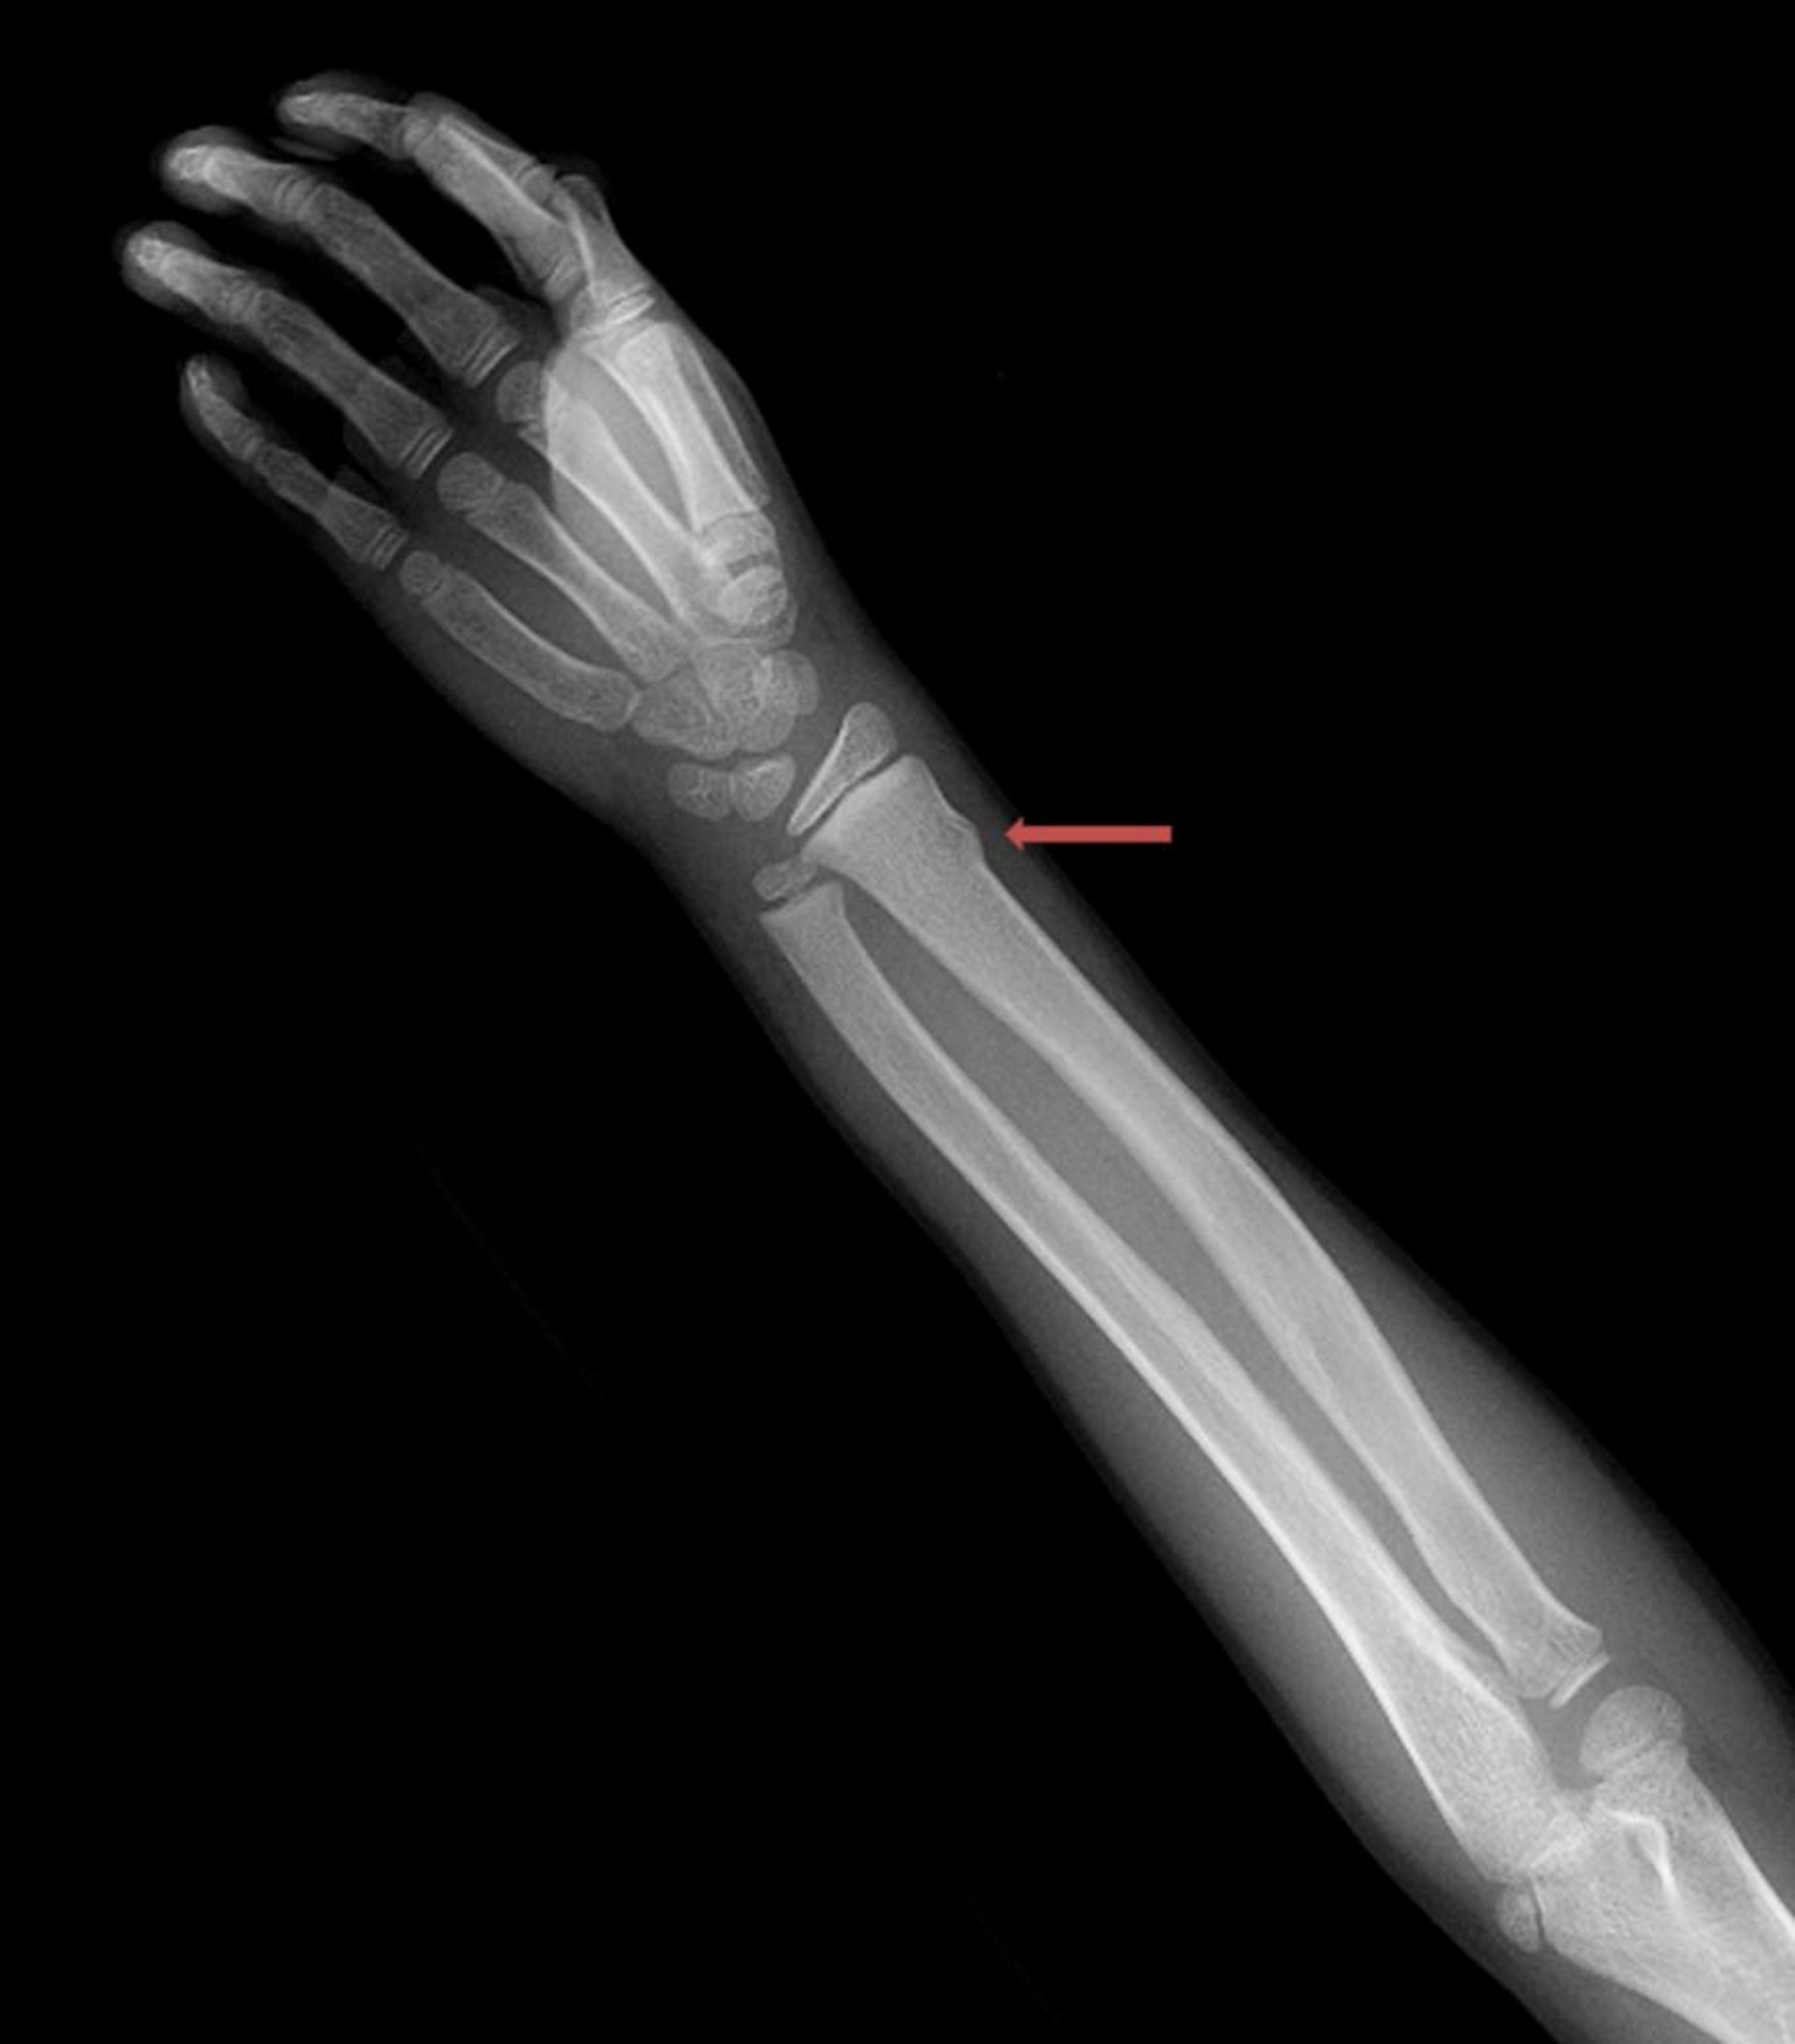

Компресійний веретеноподібний перелом зап'ястка

Такий компресійний веретеноподібний перелом дистального відділу променевої кістки візуалізується лише у вигляді незначних нерівностей кіркового кісткового шару.